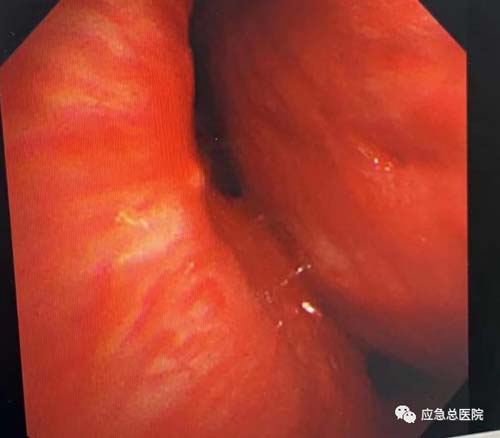

术中患者喘憋严重,无法平卧,全麻后于半坐位开始接受治疗。高鸿教授手握硬镜站在凳子上进行手术操作,硬镜刚一插入,患者心率、血压、血氧都出现下降,但随着高鸿教授迅速将硬镜插入近隆突处,心率、血压、血氧迅即出现好转,取病理、放入大Y形金属覆膜支架,仅仅6分钟,患者中央气道狭窄迅速缓解,呼吸顺畅,生命体征恢复正常,在场所有人员都松了一口气。

置入支架